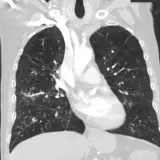

Casos totalmente interactivos con las herramientas que esperaría de un PACS: scroll, ventana, zoom, pan, mediciones, ROI y modo de pantalla completa.

• Anotaciones enlazadas

Anotaciones extensas resaltan los hallazgos clave directamente sobre los casos. Haga clic en los hallazgos enlazados dentro de la descripción del caso para saltar a su ubicación exacta en el estudio.